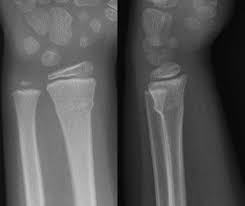

Radiograph Of Torus Fracture Of Distal Radius Anterior Posterior And Download Scientific Diagram

Radiograph Of Torus Fracture Of Distal Radius Anterior Posterior And Download Scientific Diagram from www.researchgate.net